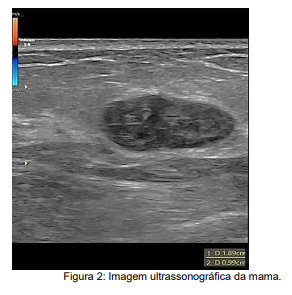

M.P.M., 22 anos, busca atendimento ginecológico ambulatorial assintomática mas muito chorosa e ansiosa, uma vez que sua sogra está em tratamento quimioterápico para câncer de mama e realizou ultrassonografia das mamas com achado ilustrado em Figura 2. Em relação ao diagnóstico mais provável e conduta, assinale a alternativa correta.

Imagem associada para resolução da questão